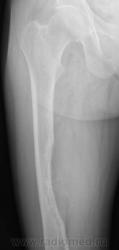

Девочка 9 лет. Родители отмечают, что 2 месяца назад девочка начала предъявлять жалобы на боли в правой пятке. Обследовались, патологии в стопе не нашли. Ребёнок постепенно начал хромать. А несколько дней назад обнаружили припухлость в в/3 бедра. Болей в бедре нет, как ночных, так и дневных. Температура не повышалась. Обратились за помощью - выполнены рентгенограммы, затем - КТ.

Злокачественная опухоль - виден луковичный периостит, инвазивный рост с лизисом кости. Но какая? Вроде бы растет из костного канала. Остеосаркома? Юинг? для этих опухолей структура какая-то больно хрящевая, мягкотканная. Хондросаркома? В таком возрасте? Почему нет клиники злокачественной опухоли кости, прежде всего - болей?

Согласна. Только периостит не луковичный, четкий лизис с козырьками Кодмена-явный признак злокачественности. А насчет болей, действительно в жизни всякое бывает, но, думаю, что ребенок не может отличить их от болей в пятке (!), а прихрамывание может быть и следствием щажения конечности.

Коллеги, давайте правильно применять термины. Периостит - окончание воспаления, применяется при остеомиелите. При опухоли - периостоз - окончание избытка, продуктивного процесса. Здесь есть "козырек Кодмена", спикулообразный периостоз, но есть так же луковичный (слоистый) периостоз, который хорошо виден на отдельных КТ-срезах. Другое дело, что для диф. диагноза опухоли (то что процесс агрессивный - сомнений не вызывыает) это, по большому счету, ничего не дает. Однако, обратите внимание на вздутие. Считаю возможны варианты телеангиоэктатической или гигантоклеточной остеосаркомы. Так же не считаю возможным исключить саркому Юинга.

Да, рентгенкартина неоднозначна, конечно, в первую очередь надо исключать зло (Юинга, остеогенную), но не уверена на 100%, что это они, спикул нет, есть луковичный периостит ниже основного очага, но это не критерий злокачественности, вздутие. Был бы возраст помладше, в первую очередь подумала бы о гистиоцитозе или туберкулезе. Еще мысли об аневризмальной кисте и ГКО. Очень хочется узнать результаты гистологии.

При такой протяженности разрушения кортикального слоя и объёме мягкотканого компонента, да и вздутии кости, что здесь может быть кроме Зла? Однако гистология интересна.

Такой вариант тоже возможен, но как мне кажется, менее вероятен. Сама по себе АКК вполне возможна. Но, всё-таки, луковичный периостоз и Кодмена никак, кроме как наличием злокачественности не объяснишь... Слишком уж они явные.